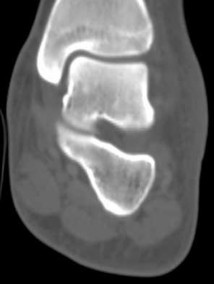

Figures 1a through 1c

Tarsal coalitions occur when primitive mesenchymal cells fail to differentiate and form the

normal articular separations between the tarsal bones of the hindfoot. Overall incidence is difficult to determine because many affected people are minimally symptomatic or asymptomatic. Symptomatic tarsal coalitions typically present in adolescents as a painful flatfoot; however, there are a number of possible presentations, and occasionally symptoms do not appear until adulthood. Most tarsal coalitions are between the calcaneus and the navicular (CN) and the talus and the calcaneus (TC). Although most TC coalitions are across the middle facet, posterior facet coalitions do occur. Plain radiographic evaluation of suspected tarsal coalition is the mainstay for diagnosis. However, coalitions can be bony or fibrous, and making the diagnosis can be difficult. The addition of CT images to distinguish bony definition and MR images to decipher soft tissue can aid in diagnostics. Bony coalitions appear as definite bony bridging between the bones, while fibrous coalitions are suspected when distortion of the bony anatomy is seen. Bony coalitions are best seen on the oblique view (CN) and Harris axial view (TC). There are a number of secondary signs such as the anteater (AE) sign (elongation of the anterior process of the calcaneus as it extends to the navicular as seen on the lateral view [CN]). talar beaking (traction spur of the talar neck thought to result from abnormal stresses as seen on the lateral view [both CN and TN]), and the “C” sign (a continuous cortical contour from the medial talus to the sustentaculum tali [ST]) as seen on the lateral view (TC). A number of newer signs are not as well known, such as a broad mediolateral dimension of the navicular on the anteroposterior (AP) view (the

navicular is wider than the talar head [CN]), nonvisualization of the middle facet on the lateral view (TC), the brick sign (a normal ST is flat, but a distorted ST is enlarged and curved [CN]), and a tapered lateral navicular bone as seen on the AP view (the medial navicular [CN] is much thicker than the lateral navicular).

Figure 1a shows talar beaking (TB), an AE, and an open middle facet (MF). Figure 1b shows a wide navicular (WN), and Figure 1c shows an abnormal articulation between the calcaneus and the navicular, all consistent with a CN coalition.